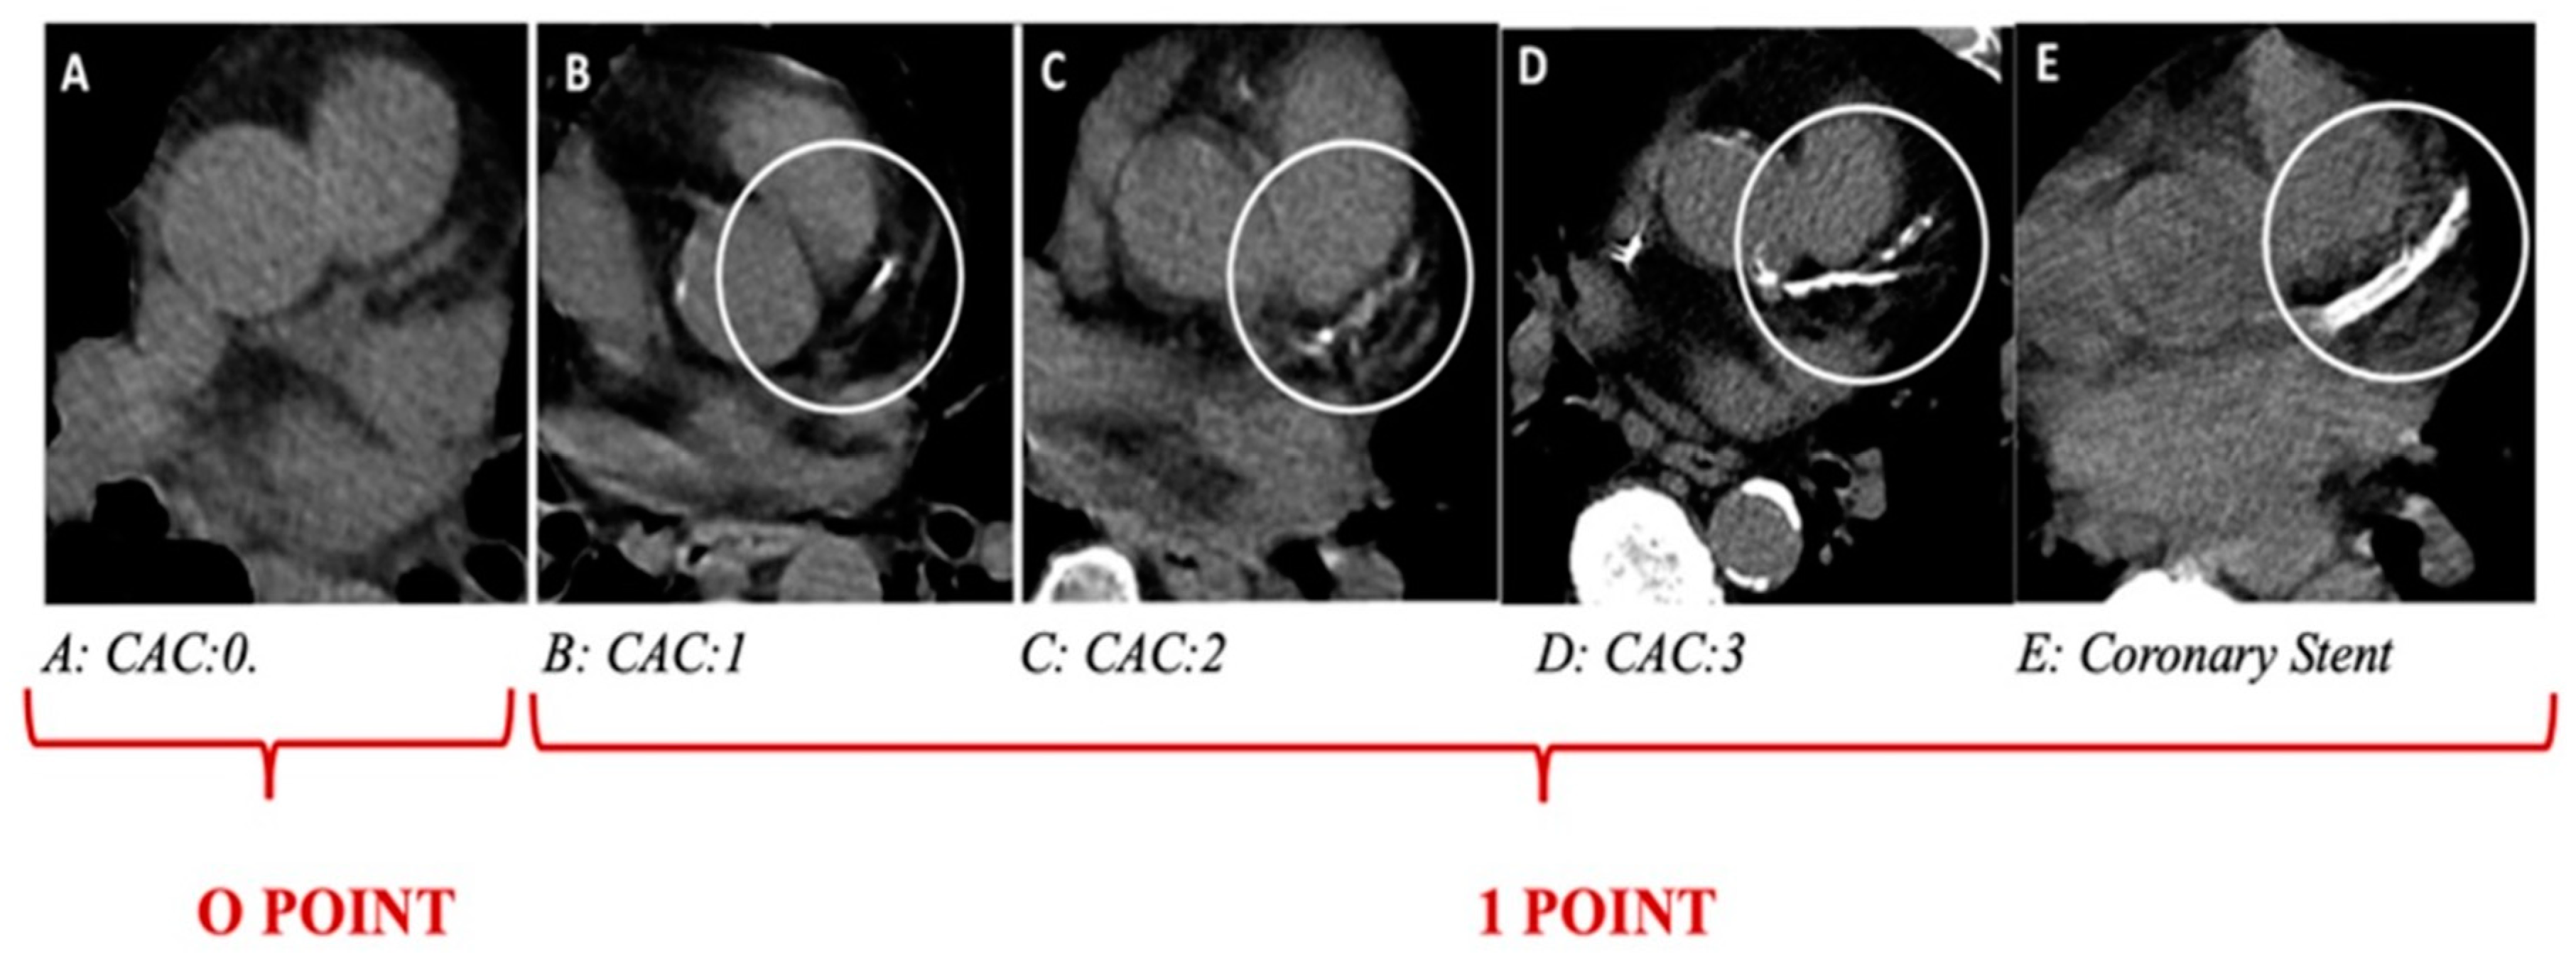

- Shemesh, J.; Henschke, C.I.; Shaham, D.; Yip, R.; Farooqi, A.O.; Cham, M.D.; McCauley, D.I.; Chen, M.; Smith, J.P.; Libby, D.M.; et al. Ordinal scoring of coronary artery calcifications on low-dose CT scans of the chest is predictive of death from cardiovascular disease. Radiology 2010, 257, 541–548. [Google Scholar] [CrossRef] [PubMed]

| Thorax CT-CACS | 3.5 (1–6.7) | 0 (0–3) | <0.001 |

| Thorax CT-CACS +, n (%) | 84 (%81) | 100 (%45) | <0.001 |

| Thorax CT—aortic calcification +, n (%) | 86 (%82.7) | 103 (%46.6) | <0.001 |

| Thorax CT CAC + aortic calcification + | 5.28 | 3.13–8.91 | <0.001 | 3.85 | 1.69–8.78 | 0.001 |

| C | CACS + Aort calcification + | 1 point |